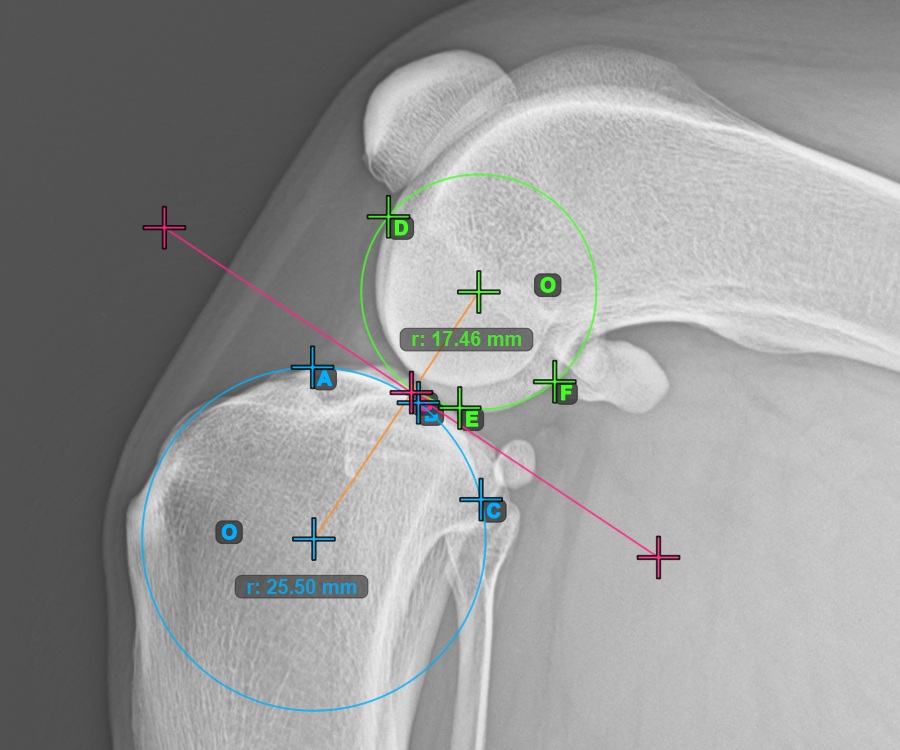

The image below represents a typical placement of the three points on the Condylus Medialis Tibialis.

Mark the three points on the main condylus of the femoral bone (Condylus Femoris). Regardless of the order, make sure to mark the most cranial point, the most caudal point and the midpoint of the Condylus Femoris. A circle will be automatically constructed based on the three placed points.

The image below represents a typical placement of the three points on the Condylus Femoris.